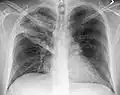

Normal lateral CXR -